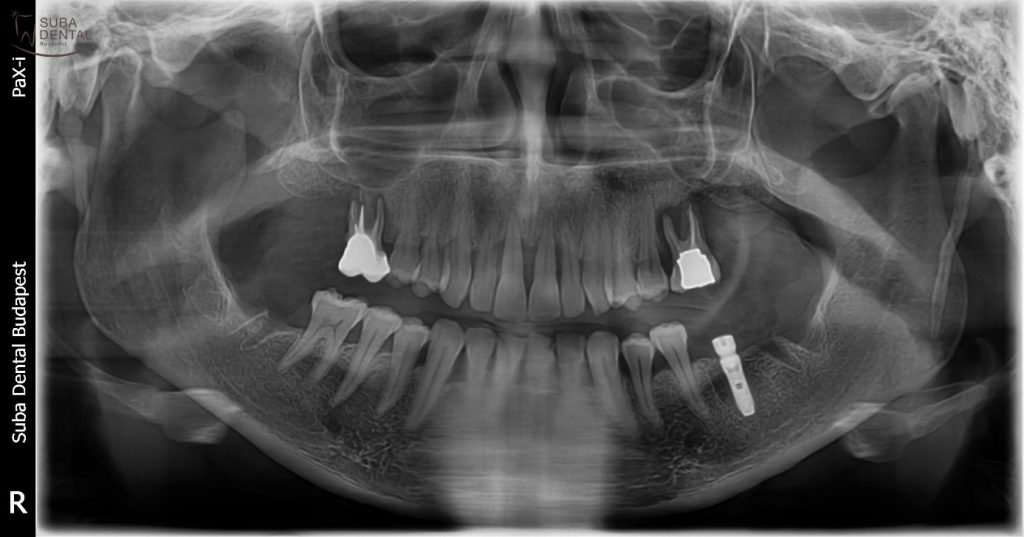

Páciensünknek az első konzultáció alkalmával egy panorámaröntgent készítettünk, és megvizsgáltuk a fogak és a fogágy állapotát. Az első vizsgálat során kiderült, hogy a felső, még meglévő őrlőfogait el kell távolítani, mert olyan nagy gyulladás van a gyökerek körül, amit már nem lehet kezelni, és az egyetlen megoldás a fogeltávolítás. Ezek a gyulladások fogászati gócok, melyeket feltétlenül kezelni kell, mert sok más egyéb, nem fogászati problémát is okozhatnak (pl.: hajhullás, bőrgyógyászati és kardiológiai szövődmények). A felső frontfogait is el kell távolítani, mert a nagyfokú horizontális és vertikális csontfelszívódás (csontrezorbció) miatt menthetetlenek. Ez nagyon megrémítette páciensünket, aki mindeddig bízott abban, hogy ez a drasztikus beavatkozás elkerülhető. Fogászati implantátumokat nem szeretne, inkább híddal pótoltatná hiányzó fogait, ha csak lehet. Ez a felső fogak esetében megoldható, de ha az alsó állcsontba fix pótlást szeretne, muszáj implantálni.

Természetesen a beültetést megelőzően CBCT (Cone beam computed tomography) felvétel készült, hogy a csontkínálatot 3 dimenzióban tudjuk vizsgálni, és alaposan megtervezhető legyen a beavatkozás. Mivel az implantátum stabilitása a beültetés során nagyobb volt, mint 30 Ncm, így gyógyulási vagy más néven ínyformázó csavart lehetett behelyezni, hogy az íny tökéletes formára gyógyulhasson a végleges felépítmény számára.

Kontroll panorámaröntgen a bal alsó nagyőrlő helyére beültetett implantátummal

Zárt kanalas lenyomatvételi fejről készült kontroll panorámaröntgen-felvétel a precíziós lenyomatvételt megelőzően

A kész panorámaröntgen-felvétel a kész felső fémkerámia, és az alsó DIO implantátumra készült fémkerámia ragasztható koronával